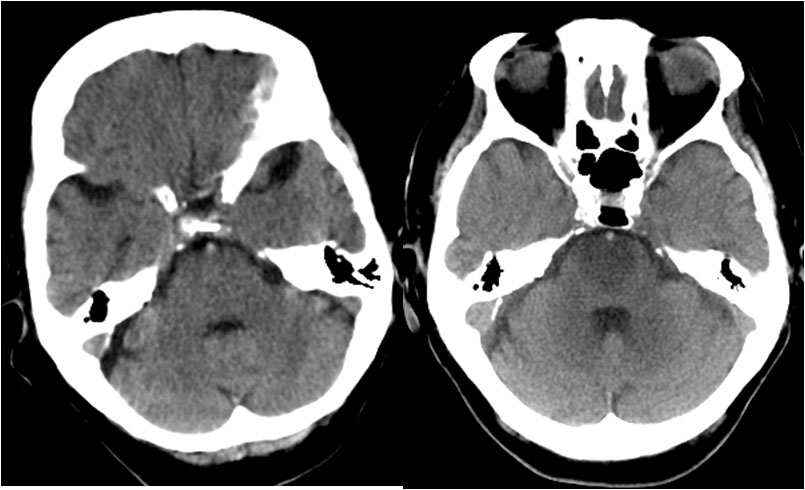

SIGNO DE LA ARTERIA CEREBRAL POSTERIOR HIPERDENSA

A la izquierda, hiperdensidad de ambas arterias cerebrales posteriores flechas). A la derecha, estudio a las 24 horas con infartos de los territorios de ambas cerebrales posteriores.

Es un signo precoz de infarto por obstrucción por trombo o émbolo que afecta a la circulación posterior cerebral. El significado de la imagen es el mismo que el de la arteria cerebral media hiperdensa, más conocido y frecuente.